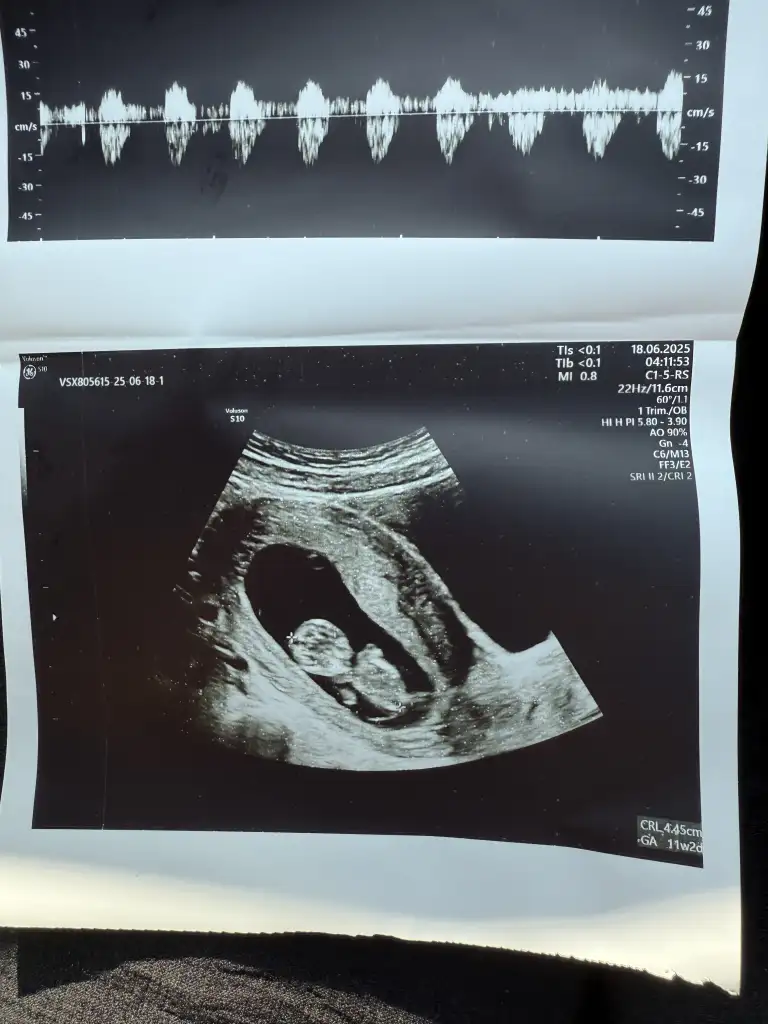

Kızlar benim bebişim de 9+0 da 😍 kese önceli haftalarsa yusyuvarlaktı şimdi şekli değişmiş. Doktor kız gibi tahmin ediyorum dedi. Sizde hislerinizi söyler misiniz 😍

• IMG_8812.webp

IMG_8812.webp

31,8 KB · Görüntüleme: 65